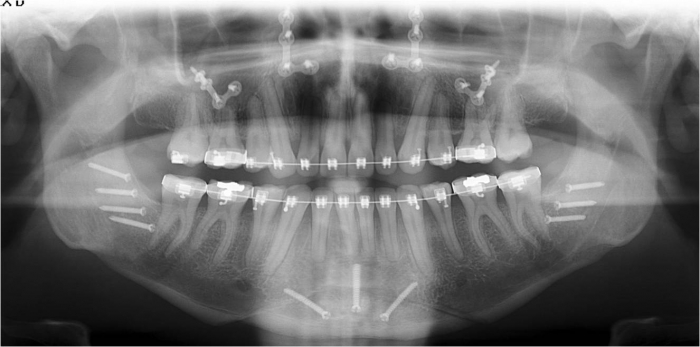

Raio x após a cirurgia